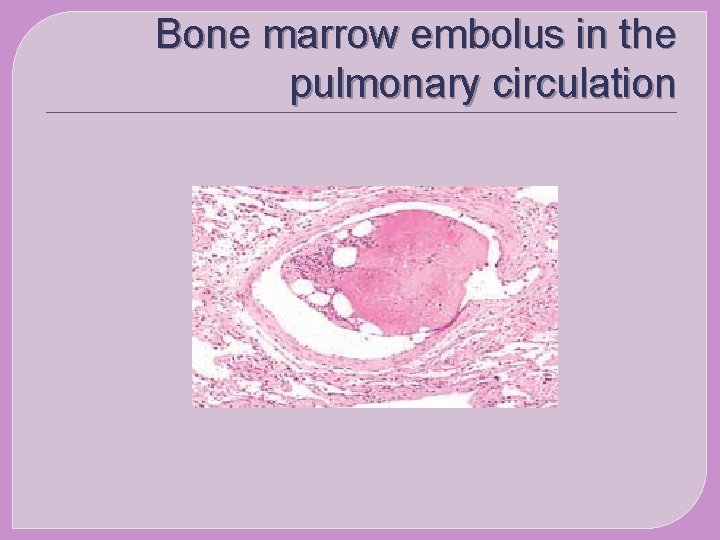

Bone marrow embolus in the pulmonary circulation